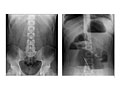

Abdominal X-Ray

Test OverviewAn abdominal

X-ray is a picture of structures and

organs in the belly (abdomen). This includes the

stomach, liver, spleen, large and small intestines, and the diaphragm, which is

the muscle that separates the chest and belly areas. Often two X-rays will be

Vancouver) or 10 days in the Rocky Mountains (Denver, Colorado). ResultsAn abdominal

X-ray takes a picture of structures and

the muscle that separates the chest and belly areas. In an emergency, the